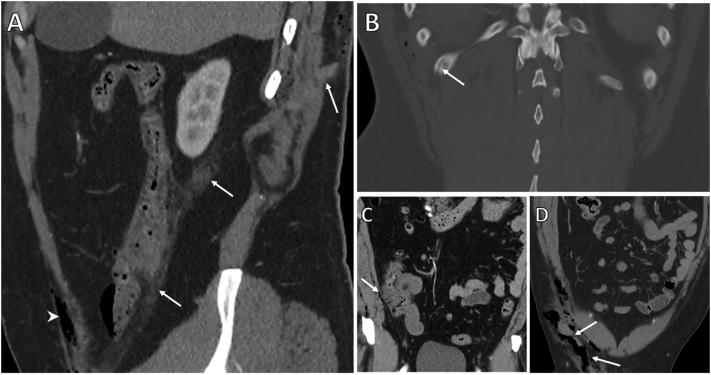

Scrotal impaling injury causing ascending colon perforation and retroperitoneal fistula.

Impalement injuries though relatively uncommon are some of the most dramatic and are known to cause significant damage due to the forces involved, the combination of blunt and penetrating mechanisms, and wound contamination. They generally occur following falls from a height, motor vehicle accidents or other high velocity mechanisms. Their management requires specific consideration to the prehospital management of the impaling object, management of any organs injured and appropriate debridement and washout of the tract. We report a case of a scrotal impalement traversing the abdominal cavity and causing a colonic injury and a rib fracture which resulted in a chronic discharging sinus from the patient's retroperitoneum.